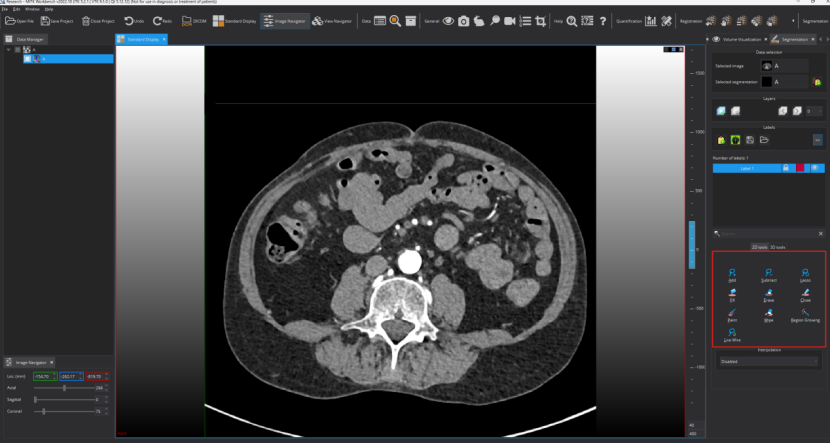

Step 6: 执行标注。按照图片的指示进行操作

点击之后可以进行标注了,这个地方可选择的标注工具比较多,下图框出部分即为标注相关工具,标注者需要进行摸索尝试一下!需要用什么标注工具,选择一下即可,然后在图上进行标注及修改